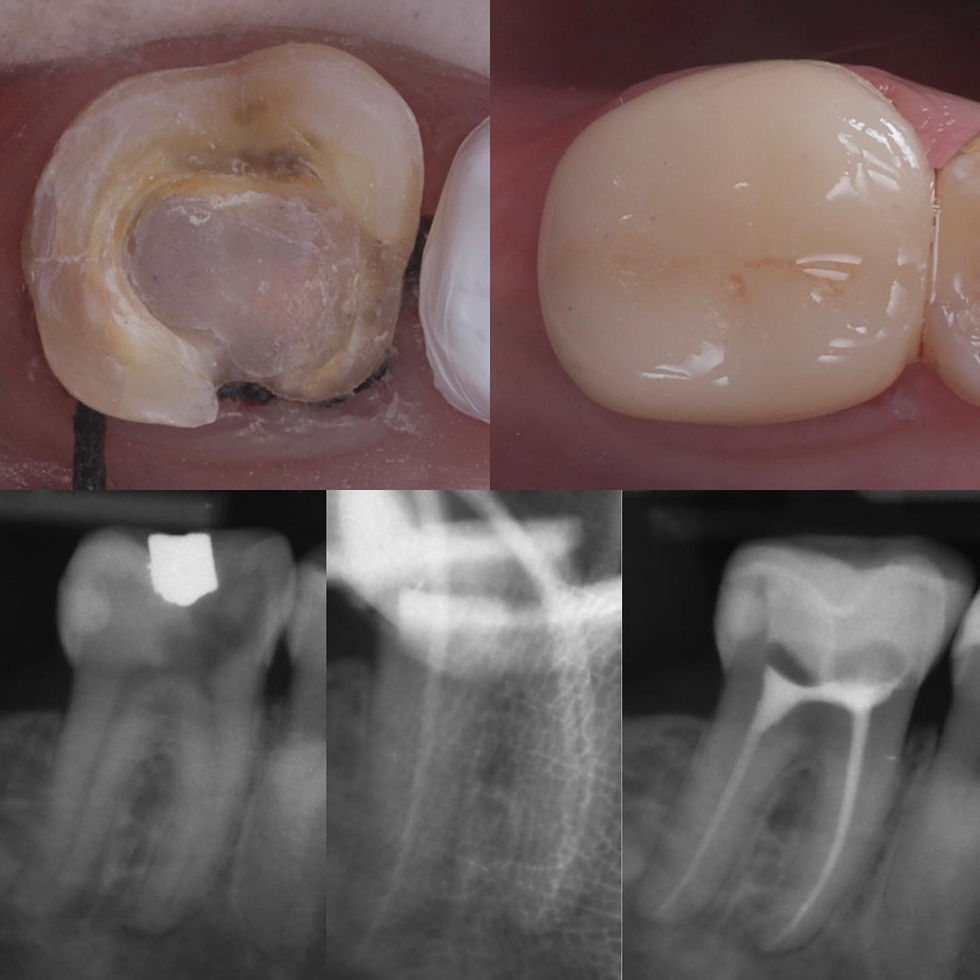

Crowns and onlays